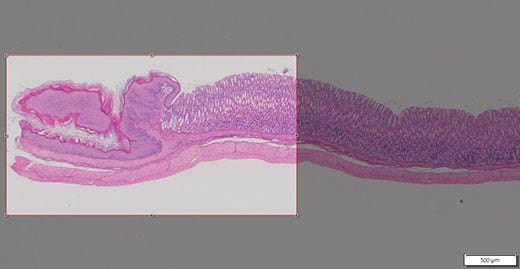

연구 그룹과 같은 특정 상황에서 고배율과 저배율로 전체 표본을 보여야 할 수 있습니다. 수동 전체 슬라이드 이미징을 통해 저배율 대물렌즈를 사용하여 전체 표본의 이미지를 캡처할 수 있습니다(그림 1). 그룹은 현미경을 설정하여 사용하는 대신에 화면의 가상 슬라이드 이미지를 관찰하여 논의할 수 있습니다. mWSI는 이미지가 전체 샘플 슬라이드에 위치해 있기 때문에 고배율로 촬영한 샘플 이미지를 논의하는 데도 유용합니다(그림 2).

그림 1: 샘플에서 표본의 저배율 이미지

학술 회의 포스터 및 논문은 종종 다양한 이미지를 표시해야 합니다. 하지만 저배율 대물렌즈로도 전체 샘플을 캡처하기가 어려울 수 있습니다. 수동 전체 슬라이드 이미징을 사용하여 다중 영역을 함께 매끄럽게 스티칭하여 명료한 오법뷰 이미지(그림 3)를 획득한 다음 타일 이미지를 트리밍하여 특정 영역을 캡처할 수 있습니다(그림 4).

그림 3: 샘플의 광범위한 오버뷰 이미지

그림 4: 오버뷰 이미지를 트리밍하여 관심 영역을 캡처할 수 있습니다